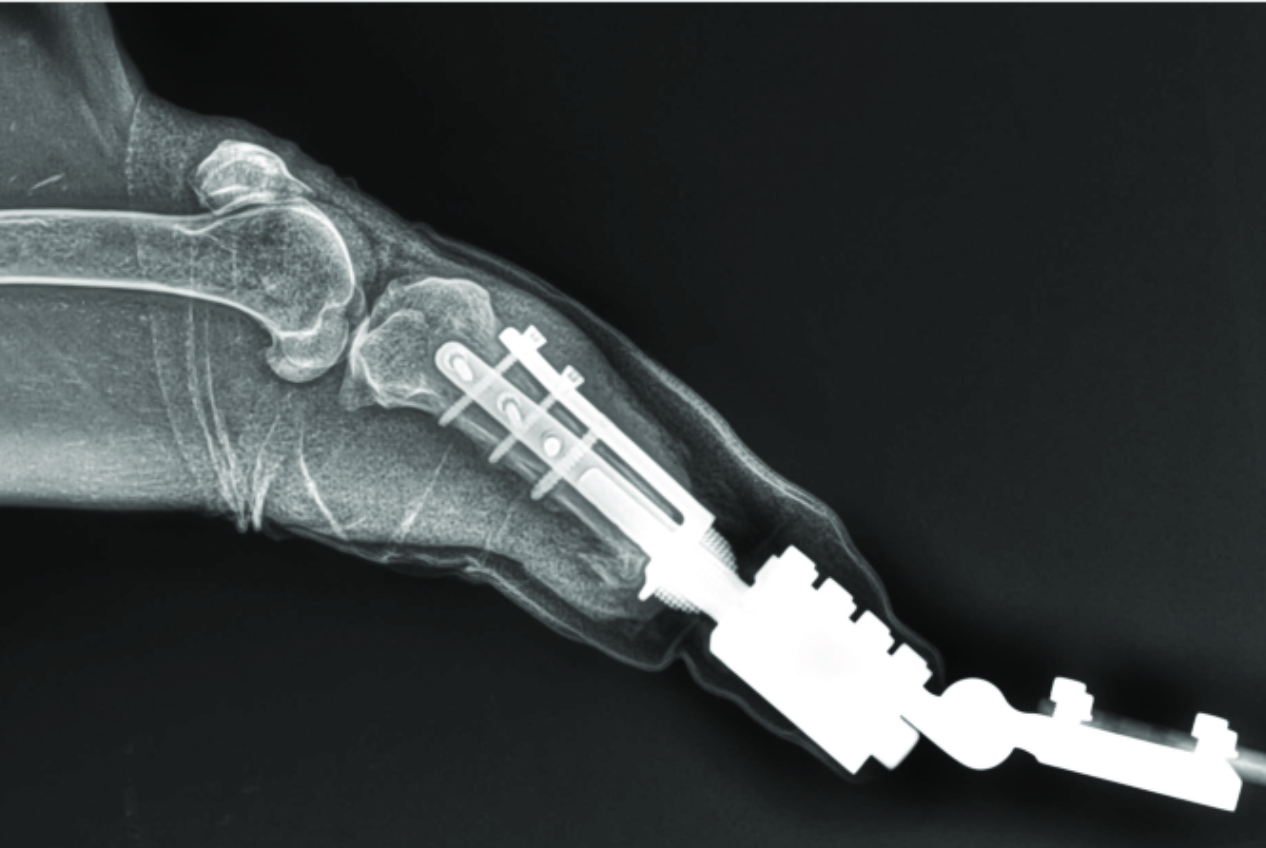

Following partial amputation, the animal was fitted with an artificial limb designed to be directly stabilised by remaining leg bone, which allowed for more efficient functionality over time, in the wild.

If you are a wild animal veterinarian you might like to know how the procedure was done. Frontiers in Veterinary Science, released a report on how it was done.